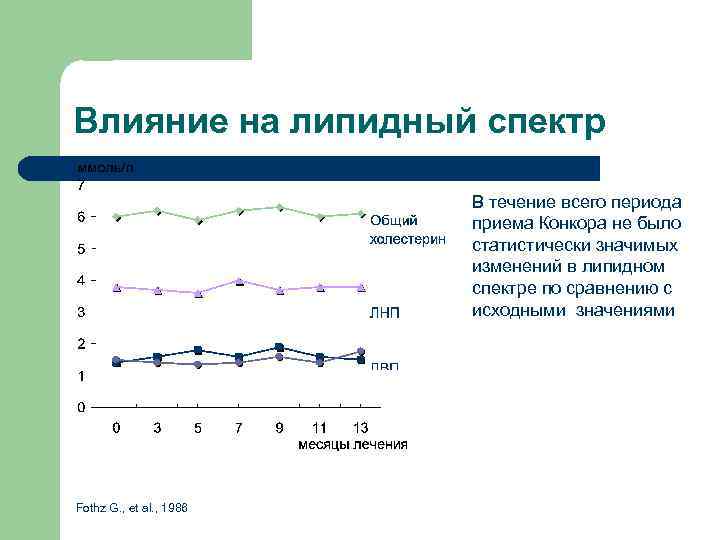

Влияние на липидный спектр В течение всего периода приема Конкора не было статистически значимых изменений в липидном спектре по сравнению с исходными значениями Fothz G. , et al. , 1986